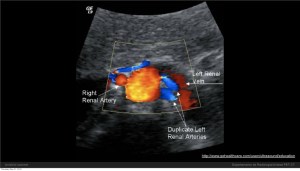

Otro estudio por ecografía muy útil es el Doppler de arterias renales, sobretodo cuando se sospecha de Hipertensión Renovascular debida a una Estenosis de Arteria Renal, en pacientes que inexplicablemente presentan elevación de la Presión Arterial, sostenida, o de difícil manejo. El doppler puede darnos una sensibilidad moderada pero el estudio ideal es la Arteriografía (Angiografía) o la Angiorresonancia.